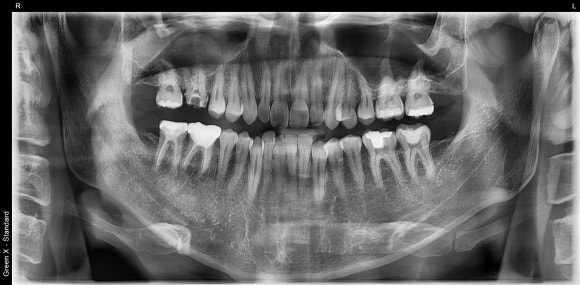

치과 검진의 기본은 파노라마.

아직도 치과에서

'엑스레이는 안 찍을게요' 하시는 분 없죠?

2025년 기준,

건강보험가입자 (대다수의 국민)이라면

10,700원만 내면

치아, 잇몸뼈, 상악동, 턱관절, 턱뼈에 대한

무궁무진한 정보를 얻을 수 있는

치과 최고의 가성비 검사입니다.

![[재신경치료] 다른 치과에서 재신경치료했는데 여전히 불편해요. 40대 남성 환자분의 재재신경치료 이야기. 관련 이미지 4](https://pub-9f2bb3498faf4d1d8714b41df24753e3.r2.dev/content/clinics/archive/nqmm0udu86/naver_blog/honeybeevuvu/assets/by_hash/fc60ebefd88ef1a1270c6ede5c5746a5ab82c18440fadfefb156768ef0bbbb46.jpg)